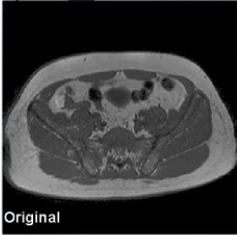

Original

Otimização de imagens de RM com melhoria de resolução, redução de artefatos e melhor definição de tecidos moles, proporcionando maior confiança diagnóstica em todas as sequências.

Original